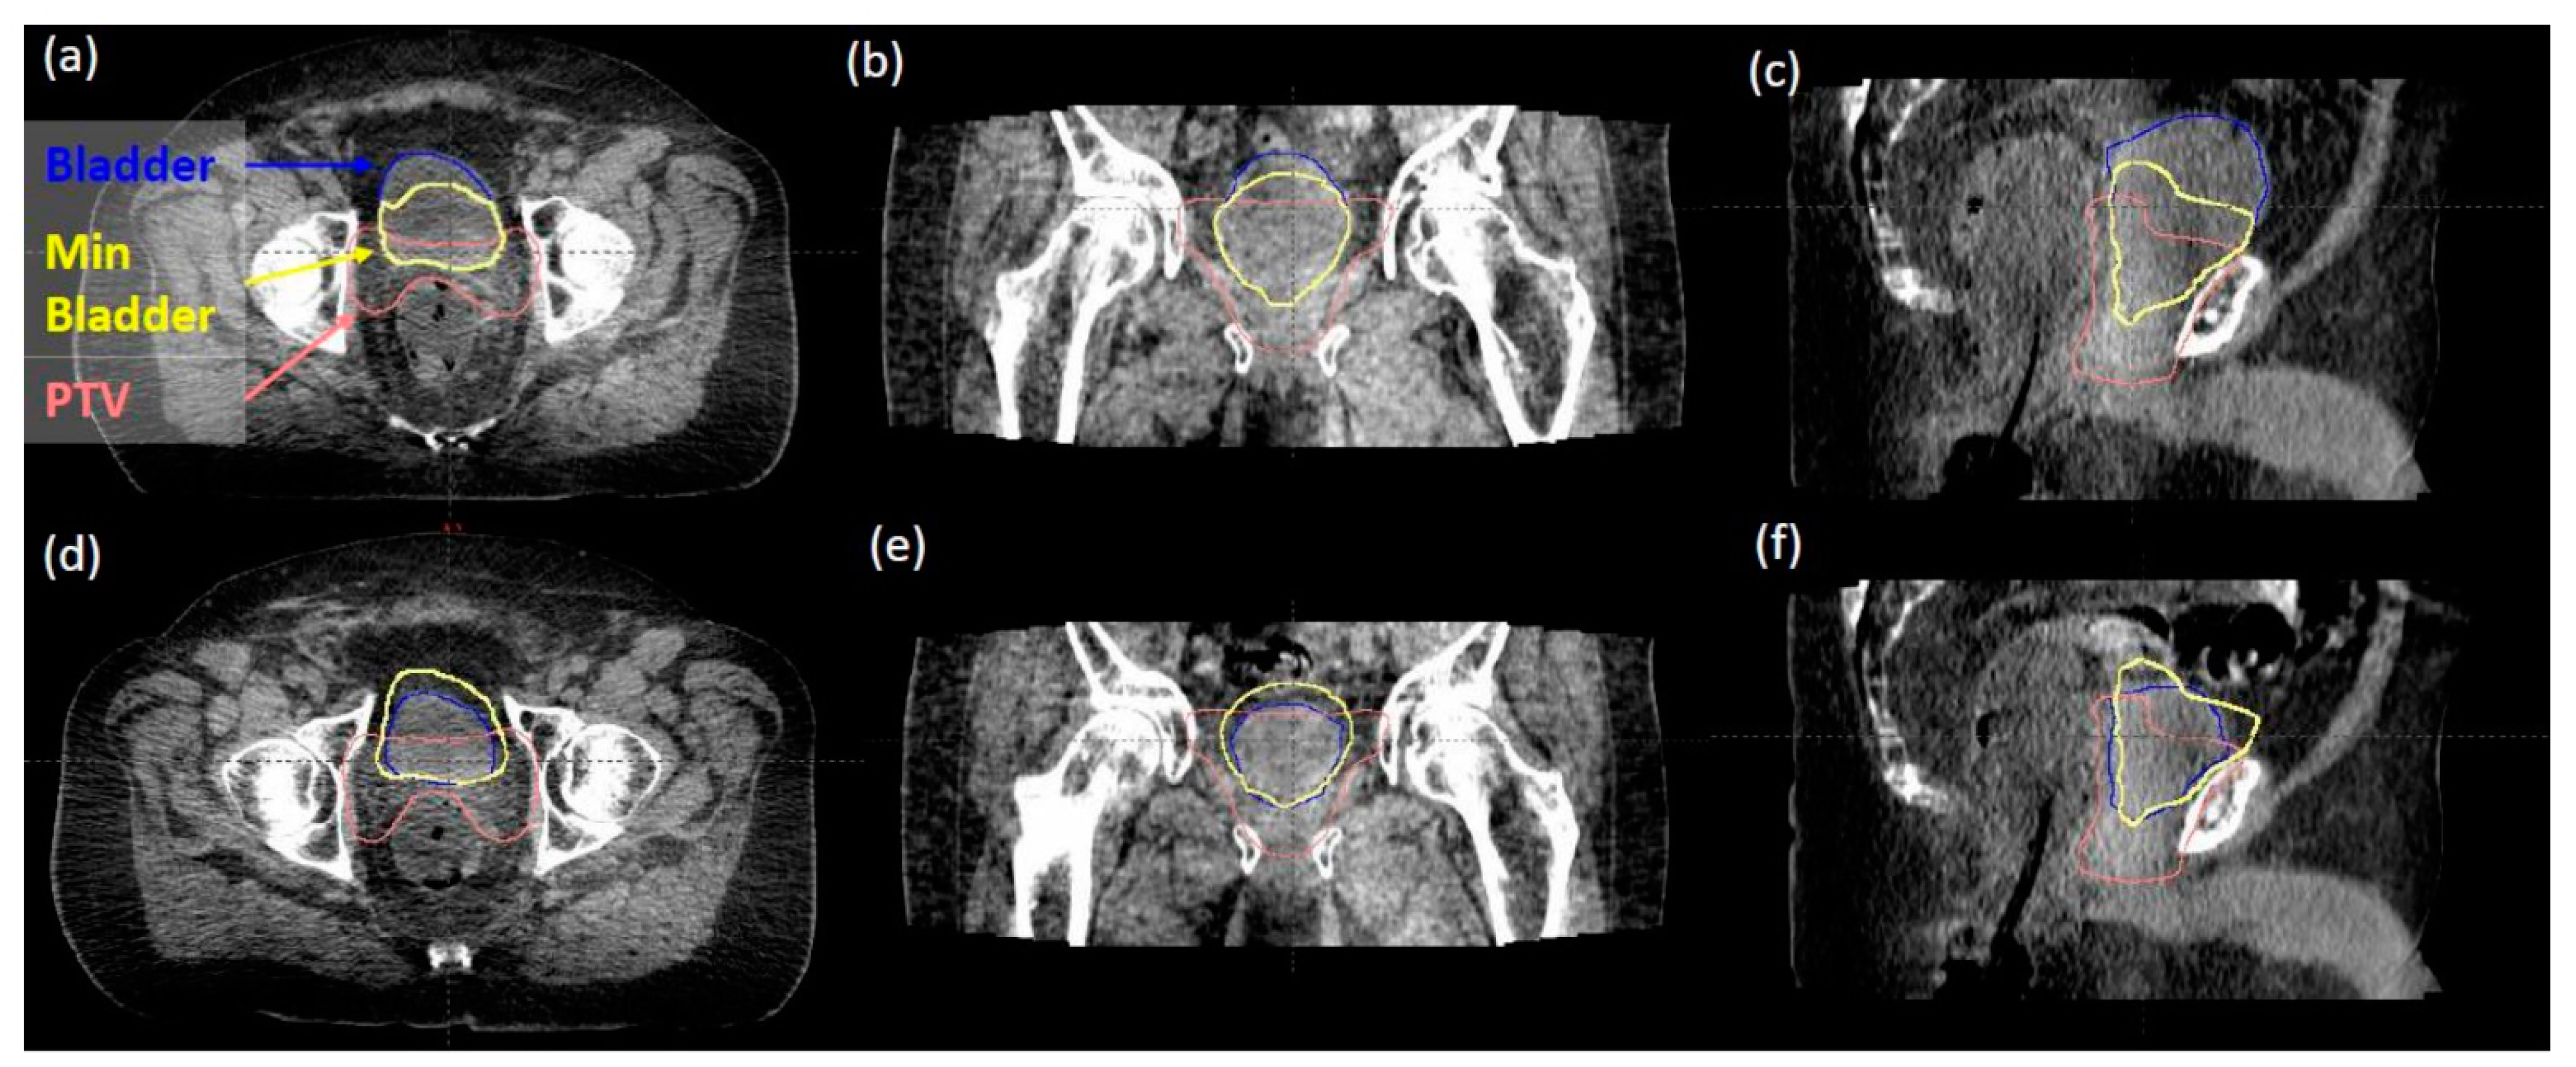

- Happersett, L.; Damato, A.; Elguindi, S.; Gorovets, D. Minimum Bladder Reference Contour to Guide Patient Setup For Prostate Radiotherapy. Int. J. Radiat. Oncol. 2020, 108, e899. [Google Scholar] [CrossRef]

- Gorovets, D.; Happersett, L.; Elguindi, S.; Della-Biancia, C.; Kollmeier, M.; McBride, S.; Zelefsky, M.; Damato, A. Minimum Bladder Reference Contour to Guide Bladder Filling for Prostate Radiotherapy. Int. J. Radiat. Oncol. 2021, 111, e274–e275. [Google Scholar] [CrossRef]